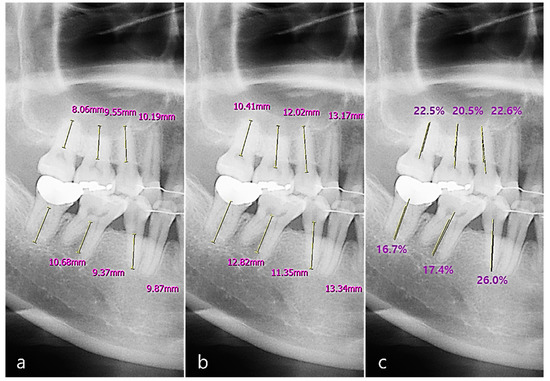

Based on the percentage rate, periodontal bone loss of the tooth was classified according to the new criteria proposed at the 2017 World Workshop on the Classification of Periodontal and Peri-implant Diseases and Conditions [16]. The classification criteria for periodontitis staging based on the RBL of the tooth were as follows. (1) RBL < 15% (in the coronal third of the root), the periodontitis was classified as stage one. (2) RBL between 15% and 33% (in the coronal third of the root) was classified as stage two. (3) RBL between 34% and 66% (in the middle third of the root) was classified as stage three. (4) RBL > 66% (extending to the apical third of the root and beyond) was classified as stage four (Figure 6) [16,25]. The average of the RBL scores of the total, maxillary, mandibular, anterior, and posterior teeth were calculated.

Figure 6.

RBL scoring on a panoramic image (a) and periapical radiographic image (b) based on the percentage rate, to classify the periodontal bone loss of the tooth for periodontitis staging according to the new criteria. The classification criteria were as follows. Score 1: RBL < 15%. Score 2: 15% ≤ RBL ≤ 33%. Score 3: 34% ≤ RBL ≤ 66%. Score 4: RBL > 66%.